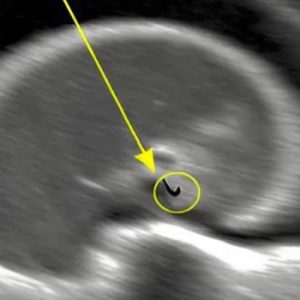

A high-risk pregnancy, our journey to welcome our son was unforgettable and amazing.

From the time I was a teenager, motherhood was never just a distant possibility—it was a future I could picture with surprising clarity. My husband and I were high school sweethearts, the kind…